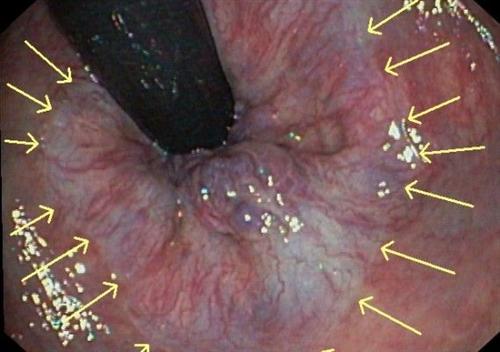

肛乳头炎算是生活中比较常见的疾病了。肛乳头位于齿线部直肠柱下端的上皮突起,呈锥体状尖朝下,如绿豆大小,呈乳白色,2-6个。受慢性炎症刺激可增大如柱状或胡桃状顶大蒂细,随排便脱出肛外,临床易误诊为直肠息肉。肛乳头肥大应积极治疗,做好预防。下面我给大家介绍一下肛乳头炎怎么办

相关图片